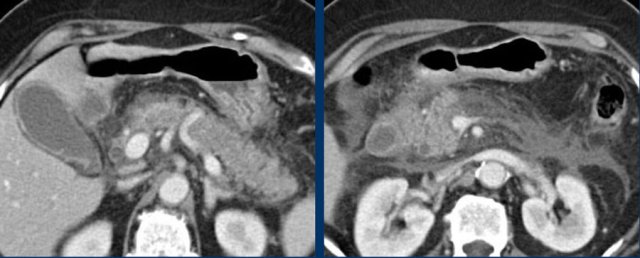

CT in acute cholecystitis

CT can be very helpful in cases with a non-diagnostic US.

These images are of an obese patient with acute RUQ pain for 6 hours. CRP 2 .

US shows a large gallbladder with sludge, no stones were visualized.

Compression of the gallbladder is unreliable due to the high position under the right costal arch.

No other US abnormalities.

CT, performed the same day, shows a large gallbladder with only discrete pericholecystic changes and no other explanation for the symptoms.

The next day CRP is 105 and repeated non-contrast CT shows a fuzzy corona around the gallbladder.

Subsequent surgery confirmed early acute cholecystitis due to a small stone in the cystic duct.